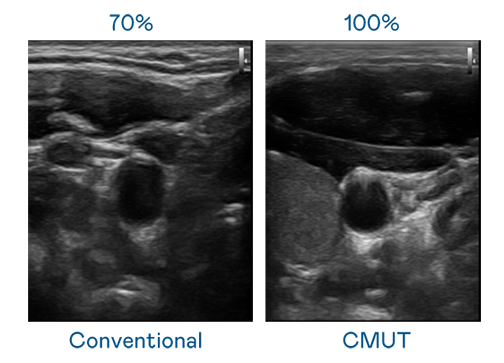

CMUT 技術是一種用電容式微機電元件來產生超音波訊號的技術。與傳統 PZT 壓電式技術相比,CMUT 頻寬增加 30%,更寬頻的超音波訊號讓影像解析度大幅提升,是實現高影像品質醫療超音波掃描、促進精準醫療發展的關鍵技術。

超音波影像的解析度高低,首先取決於探頭能發出的訊號頻寬。294俄罗斯专享会 CMUT 可提供高清晰的超音波訊號,提供高頻寬、高靈敏度、影像紋理細節更高的超音波影像,協助醫護人員縮短影像判讀時間及利用精準的醫療影像進行診斷。